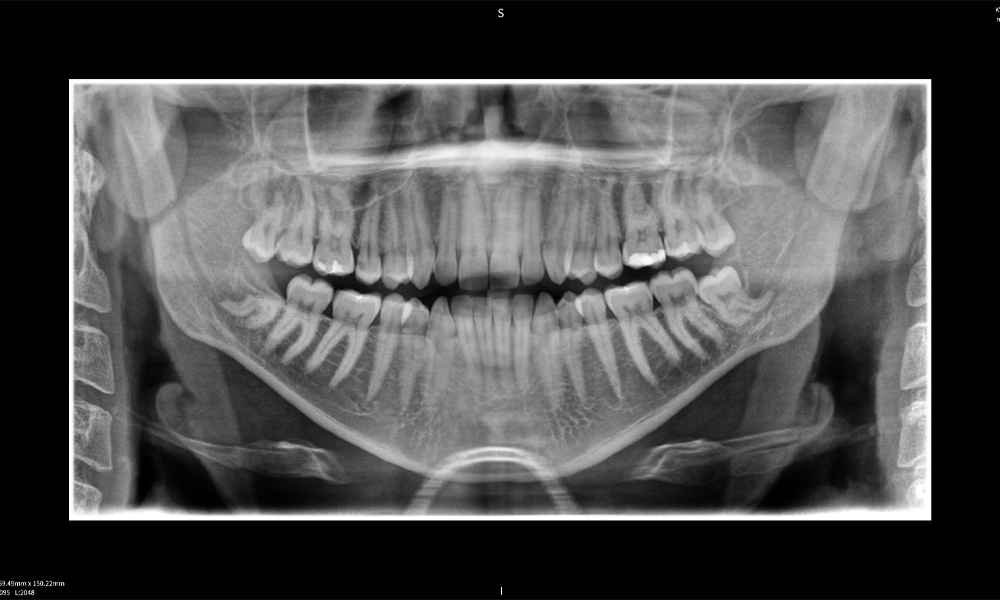

Figure e: The panoramic X-ray serves as an initial assessment tool, showing the general positioning of the teeth as well as any potential pathological changes. Notably, on the right side (tooth 48), the situation following a crown amputation performed by an external practitioner is visible. The two severely curved roots remain in close topographical proximity to the inferior alveolar nerve within the bone. This suggests a deliberate decision to avoid the increased risk of nerve injury during a complete extraction, and represents a clinically relevant finding. In summary, CBCT scans with Seethrough Max, provide crucial information about the complex anatomy and the critical relationship between the wisdom teeth and the inferior alveolar nerve. This detailed preoperative diagnostic imaging is essential for safe and successful surgical procedures in the mandibular region.